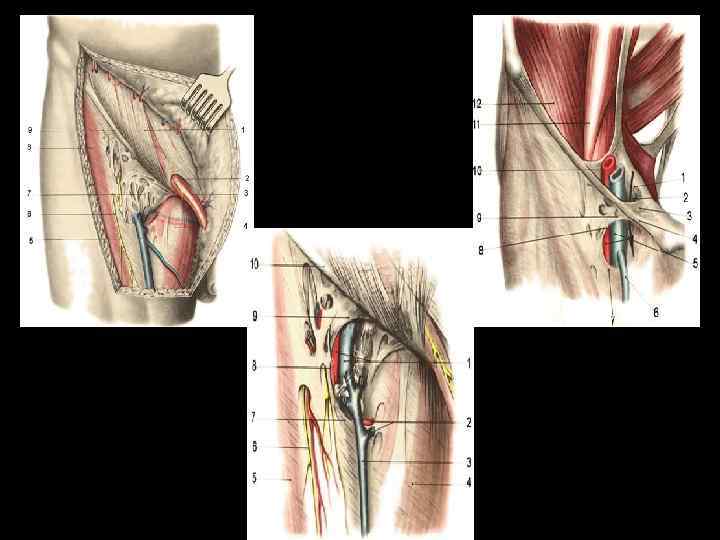

БЕДРЕННАЯ ГРЫЖА

СПОСОБЫ ПЛАСТИКИ ПРИ БЕДРЕННОЙ ГРЫЖЕ • Пластика по Бассини • Пластика по Руджи-Парлавеччи • Ненатяжная пластика